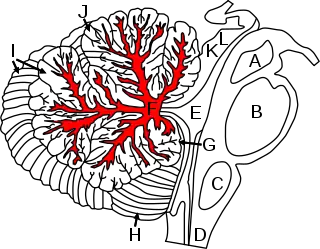

La figura muestra el cerebelo y las regiones circundantes; vista sagital de un hemisferio. A: Mesencéfalo. B: puente de Varolio. C: Médula oblonga. D: Médula espinal. E: Cuarto ventrículo. F: Arbor vitae. G: Flocculus. H: Amígdala. I: Lóbulo posterior. J: Lóbulo anterior. K: Colículo inferior. L: Colículo superior. | ||